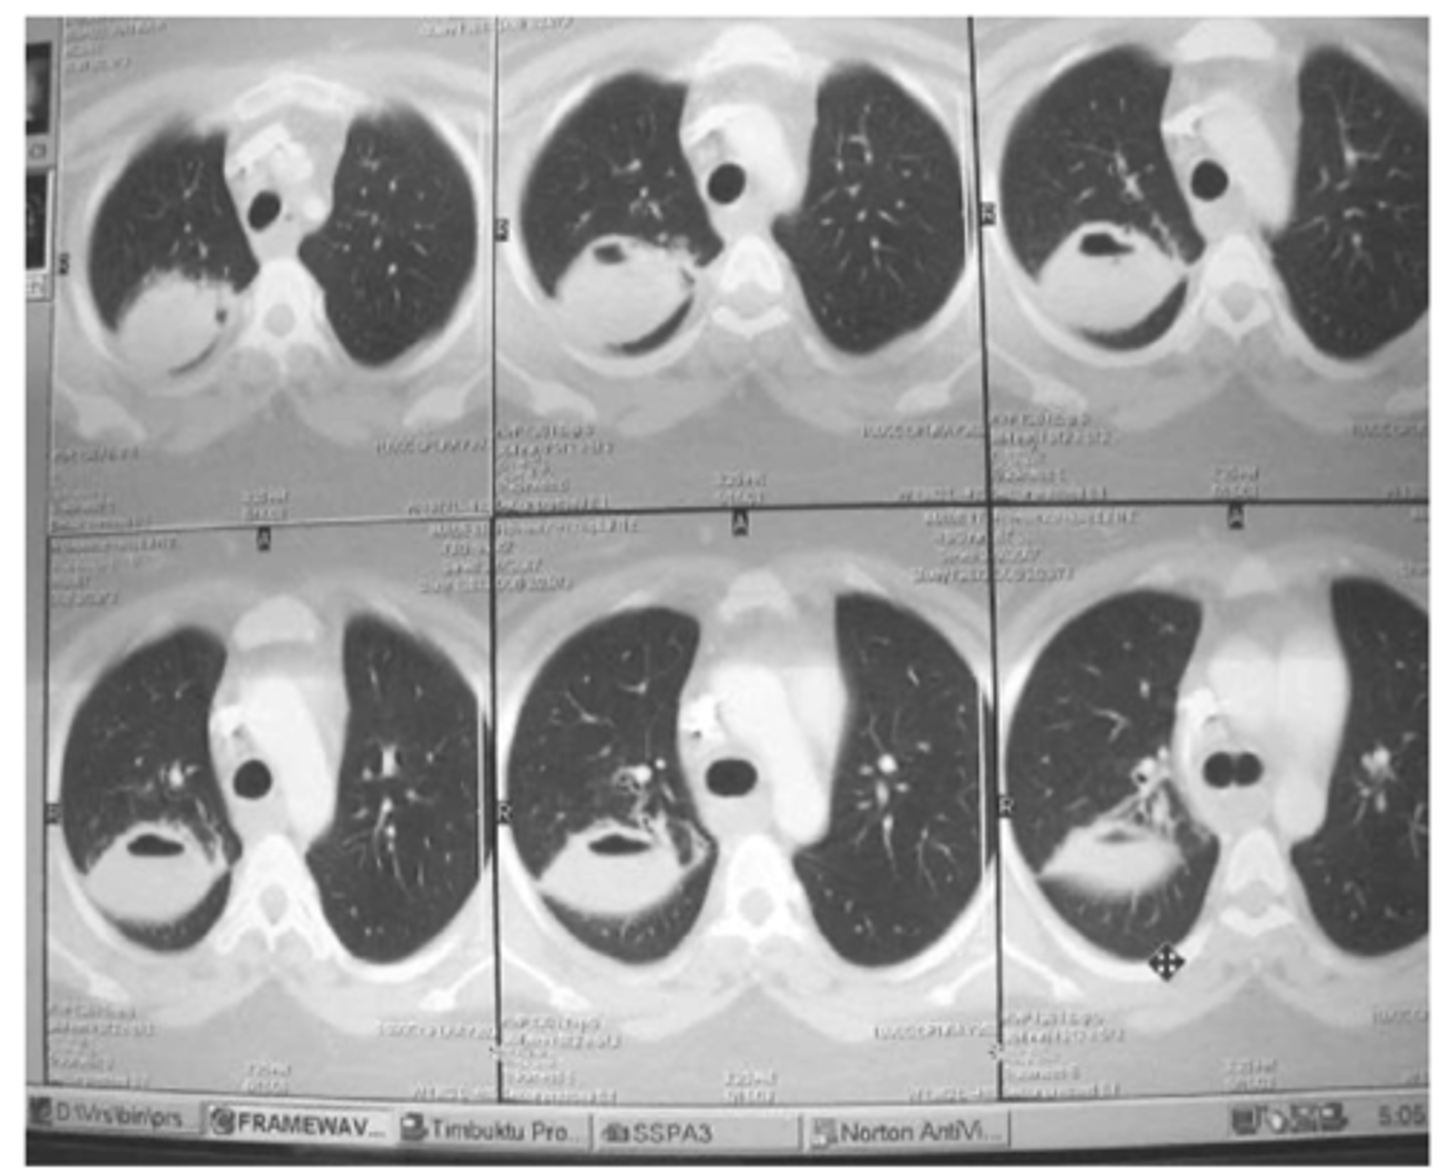

Bronchiectasis

-tram lines

Dx. What is this finding?

<p>Dx. What is this finding?</p>

Dx

<p>Dx</p>

o Difficult to see on CXR – can be seen as absence of pulmonary markings.

o Easy to see on CT scan.

What are blebs and bullae - what findings would you find on xray?

Often associated with COPD or emphysema but bullae can be present in normal asymptomatic patients. (this pt has emphysema)

What dz are blebs and bullae associated with?